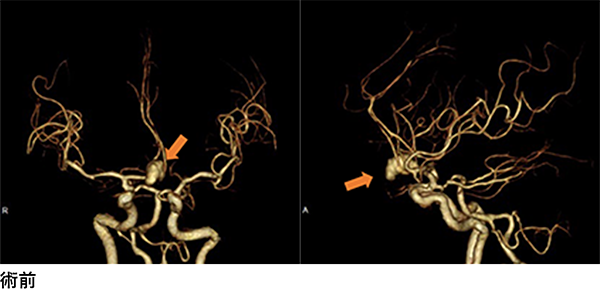

左椎骨動脈-脳底動脈の高度狭窄〜閉塞による脳梗塞で症状が著明に悪化したために行ったSTA-SCA bypass術

アテローム性脳梗塞の原因の1つとして頭蓋内動脈閉塞症があります。前述の頭蓋内動脈狭窄症がさらに進行し閉塞した場合です。いくつかの検査の結果、今後脳梗塞が起こる可能性が高いと判断された場合には手術が必要になります。手術では経皮的血管拡張術やステント留置術は行うことができず、前述のバイパス術を行います。この手術は主に、頭皮の血管(頭蓋外、骨の外側)を骨に穴を開けて脳血管(頭蓋内、骨の内側)につなぐ手術です。